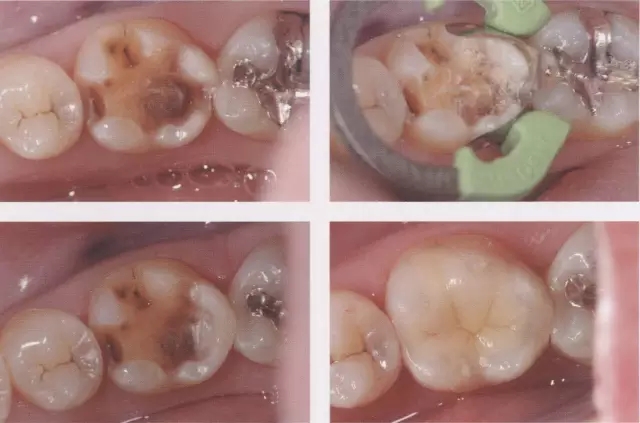

圖3 鄰接面成形困難的病例。如圖所示右下7近中傾斜,窩洞成形的遠中側(cè)有缺損(上左),所以遠中部需要在齦下做很深的成形(上右),因而選擇在遠中先進行樹脂填充后(上右)。進行MO窩洞修整后做全瓷嵌體試戴(下)。

圖4 牙頸部無變色病例。雖然變色很嚴重但由于未延伸到牙頸部(左圖),可進行齦上成形(中),最終調(diào)整到了很自然的顏色。(右)

圖5 牙頸部變色的病例。貼面發(fā)生脫離,并有前突(上圖)。去除貼面后,整體變色明顯,因而進行齦下成形,并做了1mm以上的切削。左1要進行拔髓(下左)。由于粘結(jié)對象大部分為牙本質(zhì),取模前先進行牙本質(zhì)染色,后做全瓷貼面試戴(下右)。